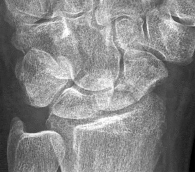

A 24-year-old man sustains a proximal pole scaphoid fracture after a fall on an outstretched hand. He is counseled regarding the high risk of nonunion and avascular necrosis associated with this specific fracture pattern. Which of the following accurately describes the primary blood supply to the proximal pole of the scaphoid?

Correct Answer: Retrograde blood flow from the dorsal carpal branch of the radial artery

Explanation:

The scaphoid receives its primary blood supply from the dorsal carpal branch of the radial artery, which enters the bone distally and provides retrograde blood flow to the proximal pole. This retrograde supply makes proximal pole fractures particularly vulnerable to avascular necrosis and nonunion.